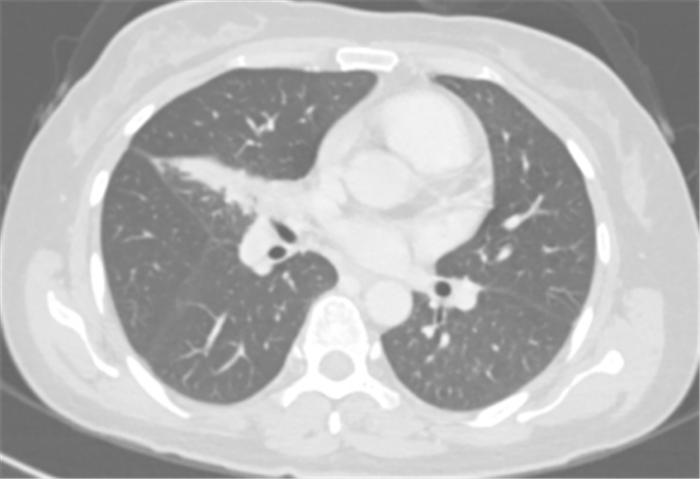

覃寿明教授团队为李女士进行了4个周期的化疗联合免疫新辅助治疗。覃寿明介绍,肿瘤的免疫治疗是通过激活人体免疫系统,依靠自身免疫机能实现杀灭肿瘤细胞和肿瘤组织。免疫治疗的作用更持久,副作用也相对更低。

经过4个周期的治疗后复查发现:李女士的病灶明显缩小,实现了降低肺癌分期。

免疫联合化疗新辅助治疗4周期后胸部CT